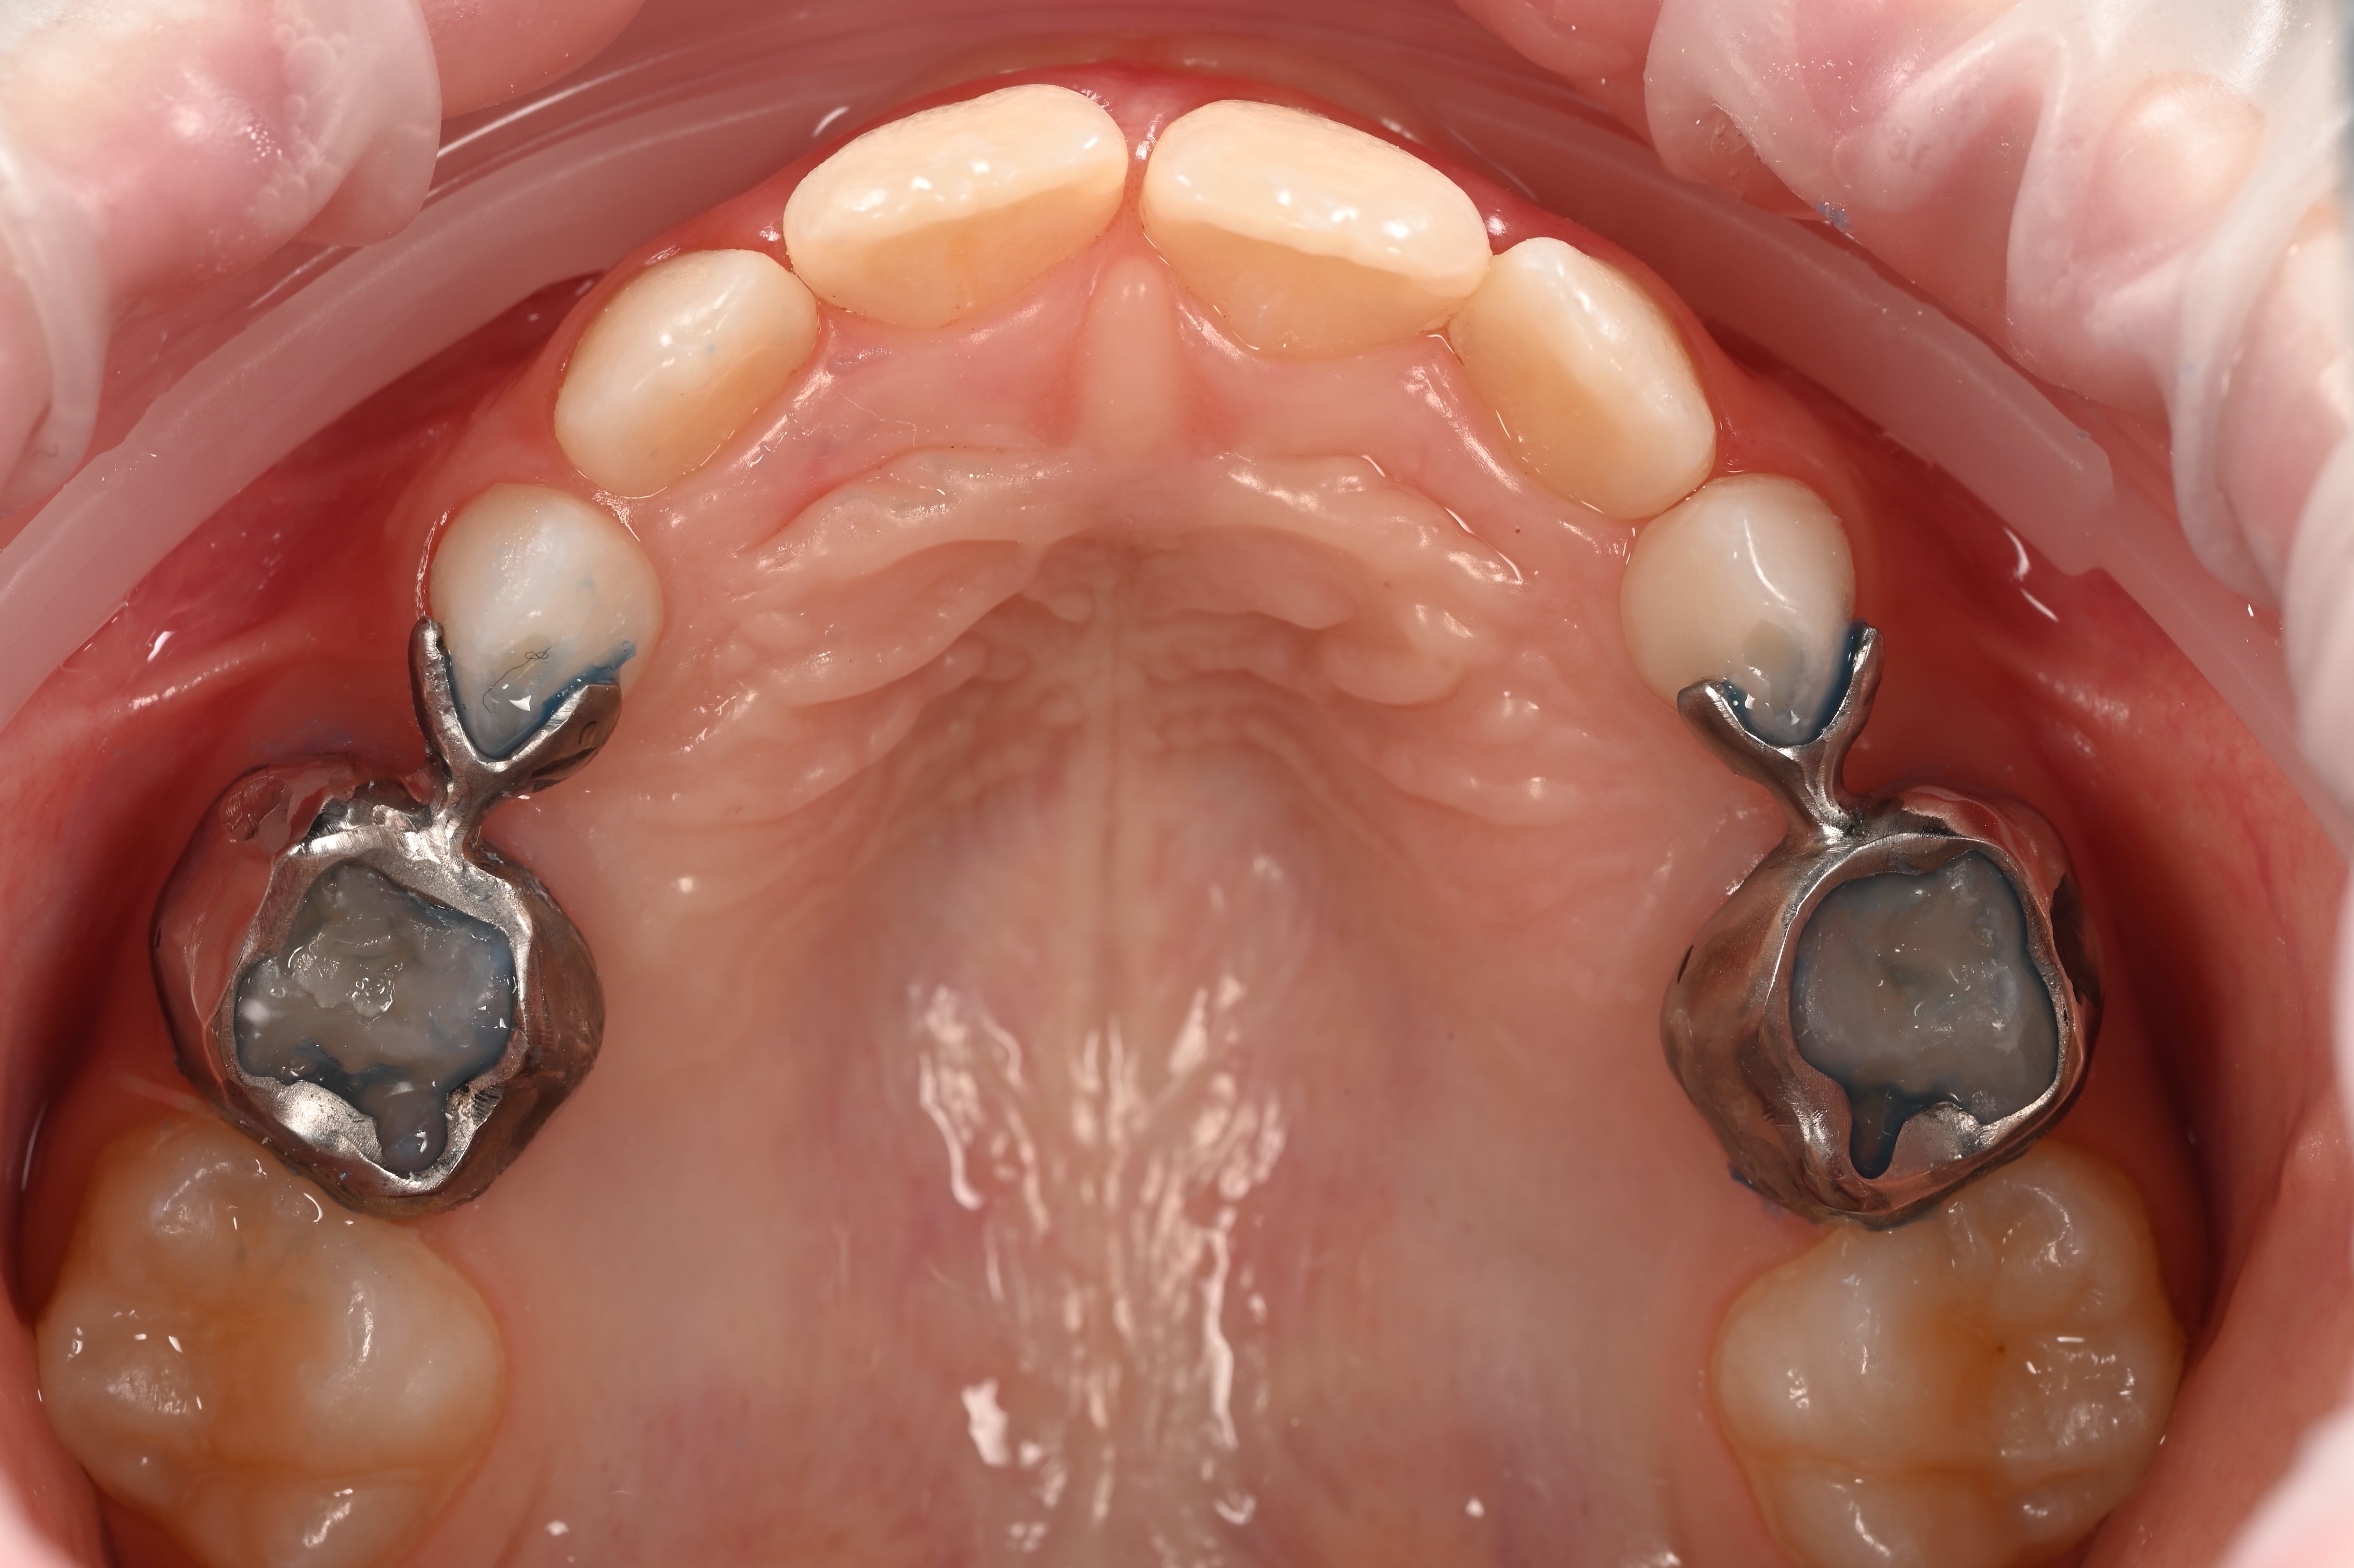

- Апарат для утримання місця — після передчасного видалення молочного зуба, щоб уникнути скупчення постійних зубів у майбутньому та, як наслідок, неправильного прикусу.